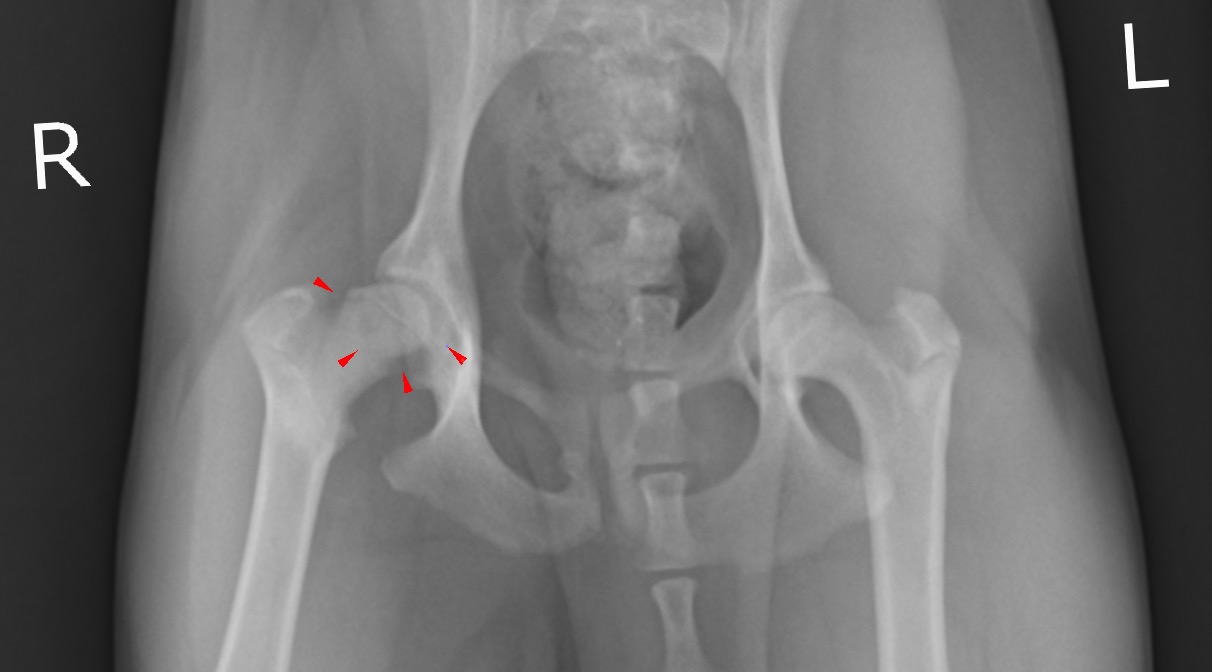

X線検査において右大腿骨頭の不整、骨萎縮、X線透過性の変化が認められ、(赤矢頭)

背景にレッグカルベペルテス病(LCPD、無菌性虚血性大腿骨頭壊死症)(以下LCPD)の存在が疑われました。

右大腿骨頭部の異常所見